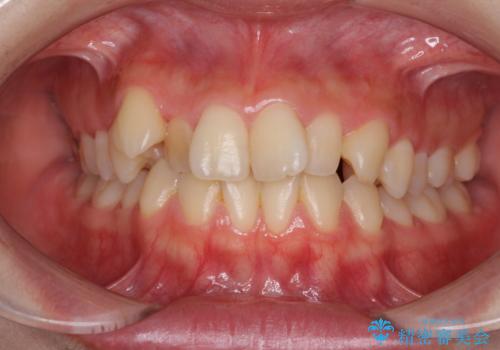

- 前歯のデコボコを気にして来院された患者様です。

本人は気づいていませんでしたが、下顎前歯が2本欠損しており、上下の歯列がアンバランスとなりデコボコになっていました。

上下のバランスを取るため、上顎左右第一小臼歯2本を抜歯し、ワイヤー矯正を行うこととしました。